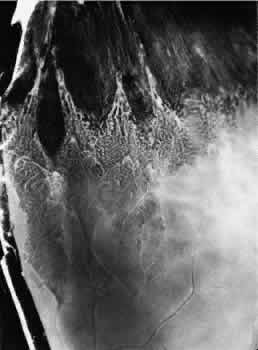

NONCYSTIC RETINAL TUFT

A noncystic retinal tuft is a short, thin internal projection of retinal tissue that usually occurs in clustersand is almost invariably located within the vitreous base. From the vitreous attachment at the apex, the tuft extends to a base that is less than 0.1 mm in diameter and unassociated with cystic retinal degeneration (Fig. 36). Histologically, a noncystic tuft is composed of altered retinal cells and proliferated glial tissue (Fig. 37).27,34 Noncystic retinal tufts are not present at birth. They are present in 72% of adult patients, are bilateral in 50% of affected individuals, and thus are present in 59% of adult eyes (see Table3). Tufts occur in all sectors, but they are most common in the inferior nasal quadrant and are almost always located in the anterior portion of the peripheral retina corresponding to the vitreous base.

Fig. 36. Noncystic retinal tufts: cluster of small surface nodules of retina within vitreous base. Surrounding retina shows nonspecific degeneration and pigment dispersion. (× 20.)

Fig. 37. Microscopic features of the lesion seen in Figure 36. Entire retina within vitreous base shows nonspecific degeneration with gliosis. Centrally, the surface is elevated and shows a plaque of dense-staining glial cells. Retinal pigment epithelium also shows irregular thinning and pigment clumping, characteristically found within vitreous base. (Hematoxylin-eosin stain; × 500.)

On clinical examination, these tufts are commonly observed as small, pointed retinal projections within the area of the vitreous base. In later life, degenerative changes within the tufts may cause the tips of the tufts to break off, producing small spherical fragments that float in the vitreous adjacent to the base. These tufts are not associated with full-thickness retinal breaks and can be considered to be innocuous.